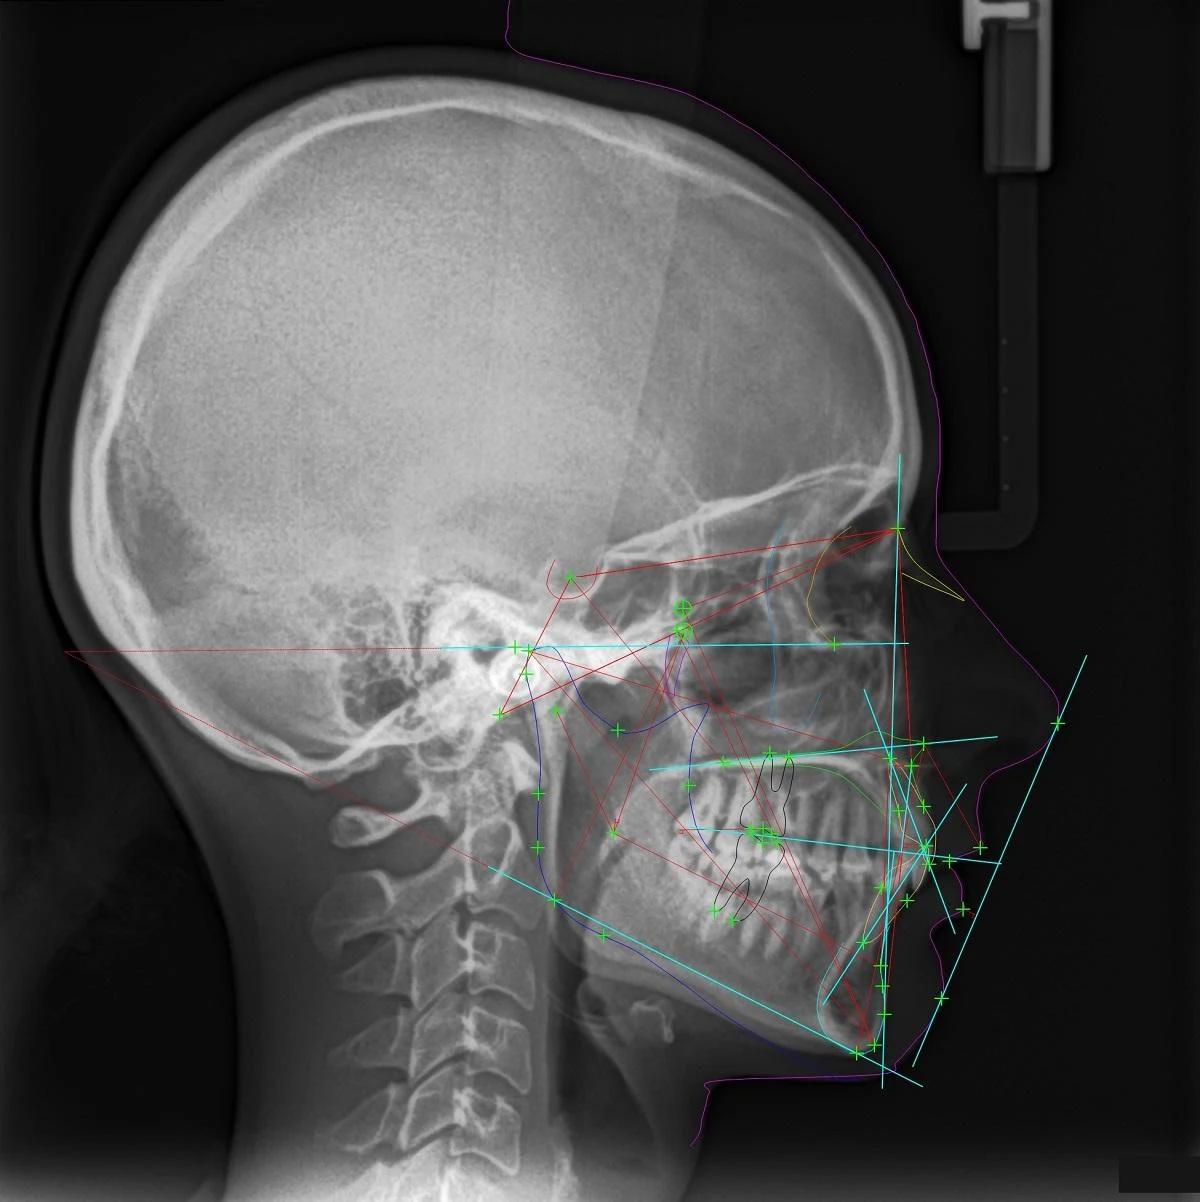

Diagnostyka ortodontyczna

Ocena cefalometryczna (zdjęcie boczne czaszki) i skaner intraoral pozwalają określić, czy przodozgryz ma podłoże zębowe czy szkieletowe. To podstawa prawidłowego planowania leczenia – bez niej każdy plan to zgadywanie.

Przodozgryz (zgryz III klasy) to wada, w której dolne siekacze stoją z przodu względem górnych przy zamkniętych zębach – relacja odwrotna do prawidłowej. Przy prawidłowym zgryzie górne siekacze zachodzą na dolne od zewnątrz. Przodozgryz może być zębowy (zęby wychylone, kości prawidłowe) lub szkieletowy (zbyt mała górna szczęka lub zbyt duża żuchwa). Ten drugi daje charakterystyczny profil z cofniętą środkową częścią twarzy i wysuniętą brodą. Ostateczne rozpoznanie i ocenę, z czego wynika wada, stawia ortodonta po badaniu klinicznym i cefalometrii (zdjęciu bocznym czaszki).